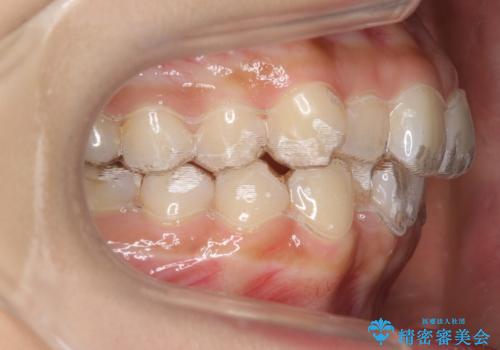

初回:上顎16ステージ 下顎22ステージ

リファインメント: 上顎23ステージ 下顎20ステージ

下の前歯のがたがたがそれなりにあったため、リファインメントを行いました。